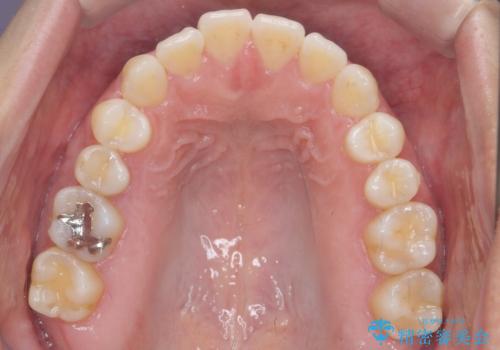

受け口、すきっ歯を インビザラインで モニター治療

- 前歯のすき間と受け口を気にして来院。

マウスピースでしっかり閉じています。

下の前歯を後方に移動するため、ゴムを上下のマウスピースにかけてもらいました。